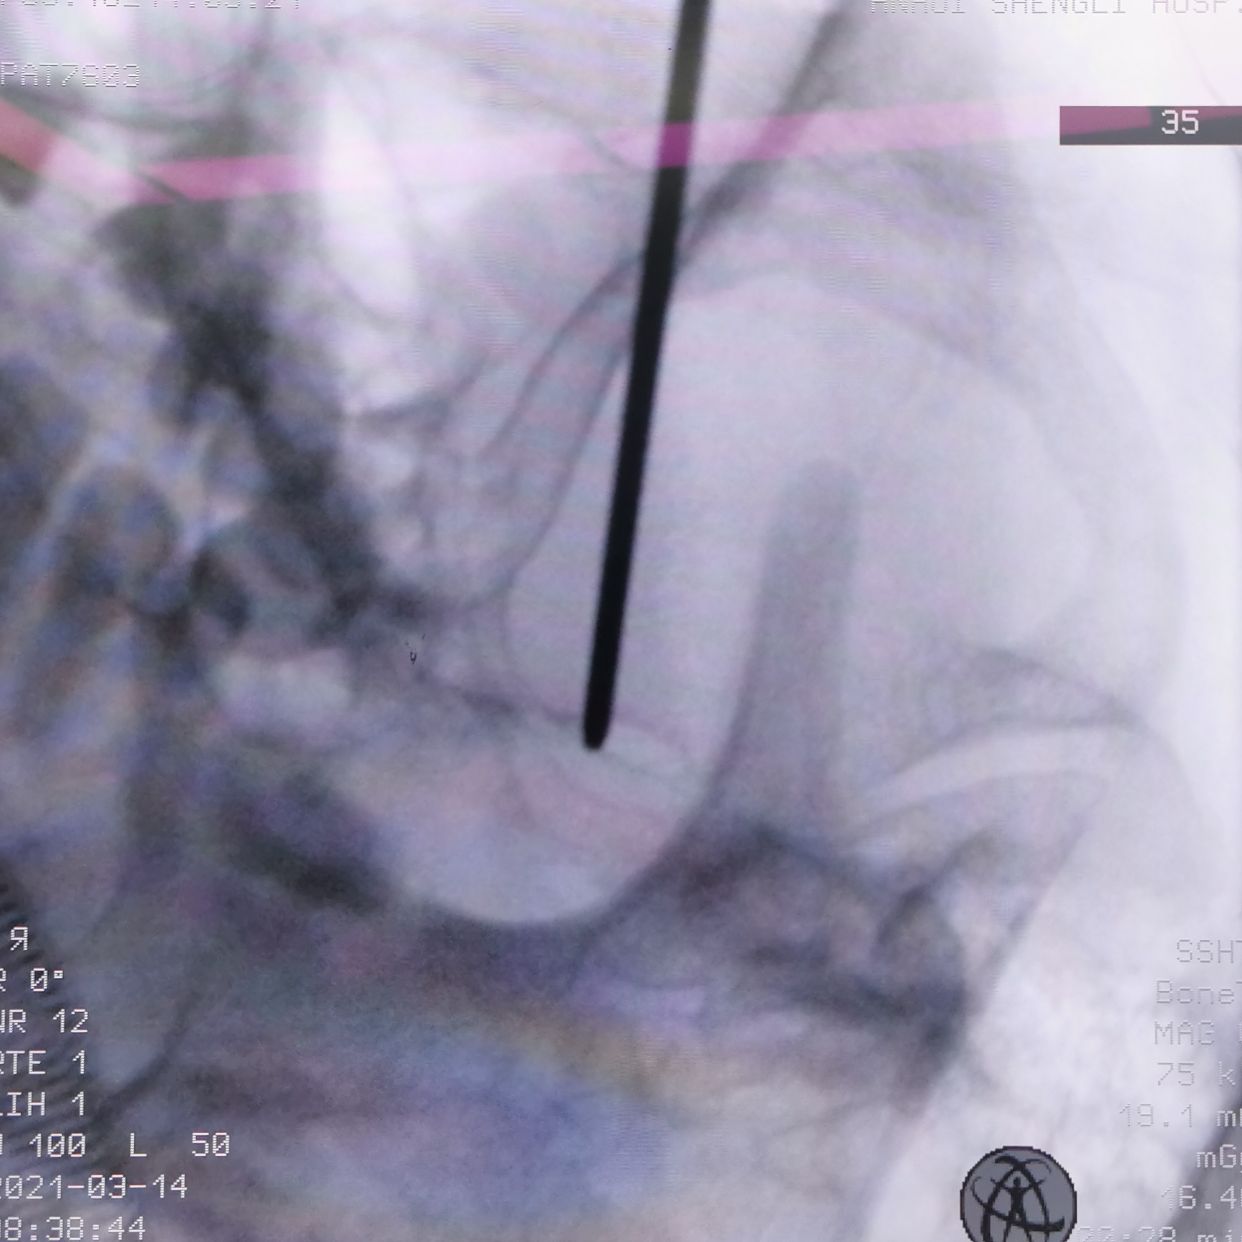

穿刺针到此,无法进入,骨质完全遮挡

改为中入路

成功